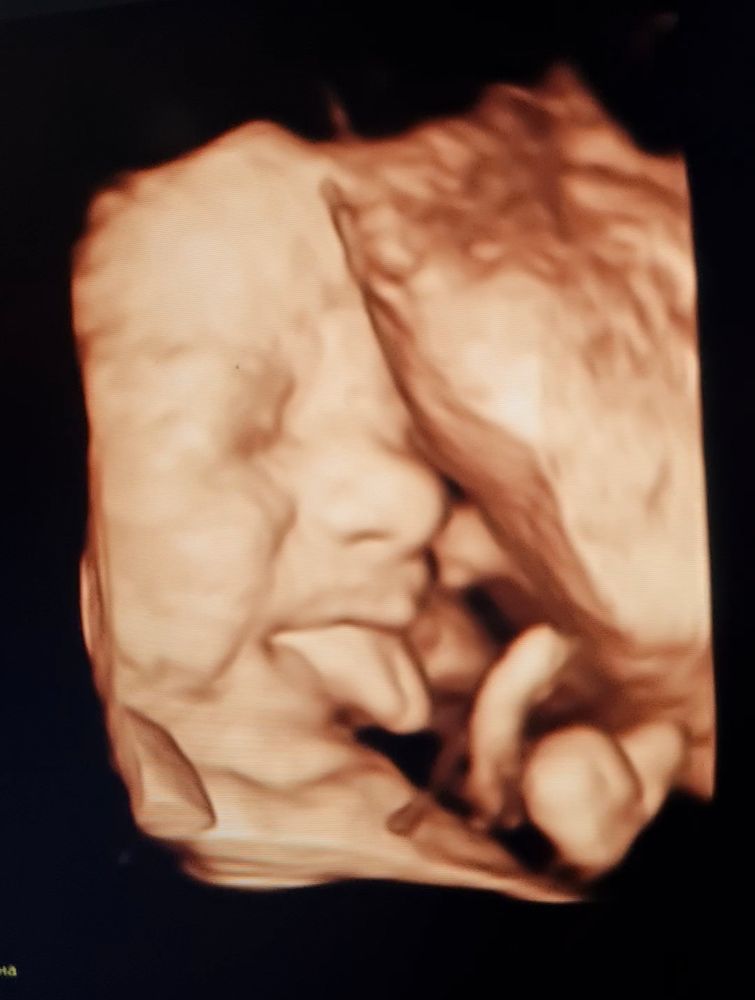

Мы родились 🥳 30.06. Родила